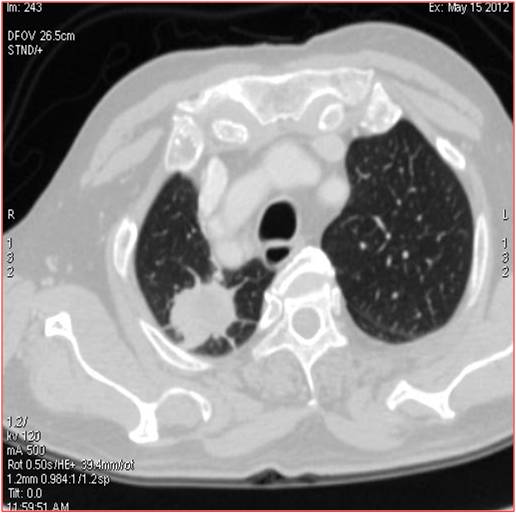

Heterogeneously enhancing irregular spiculated soft tissue mass measuring ~ 34 x 29 mm noted in the apical segment of right upper lobe. The lesion abuts the pleura posteriorly.